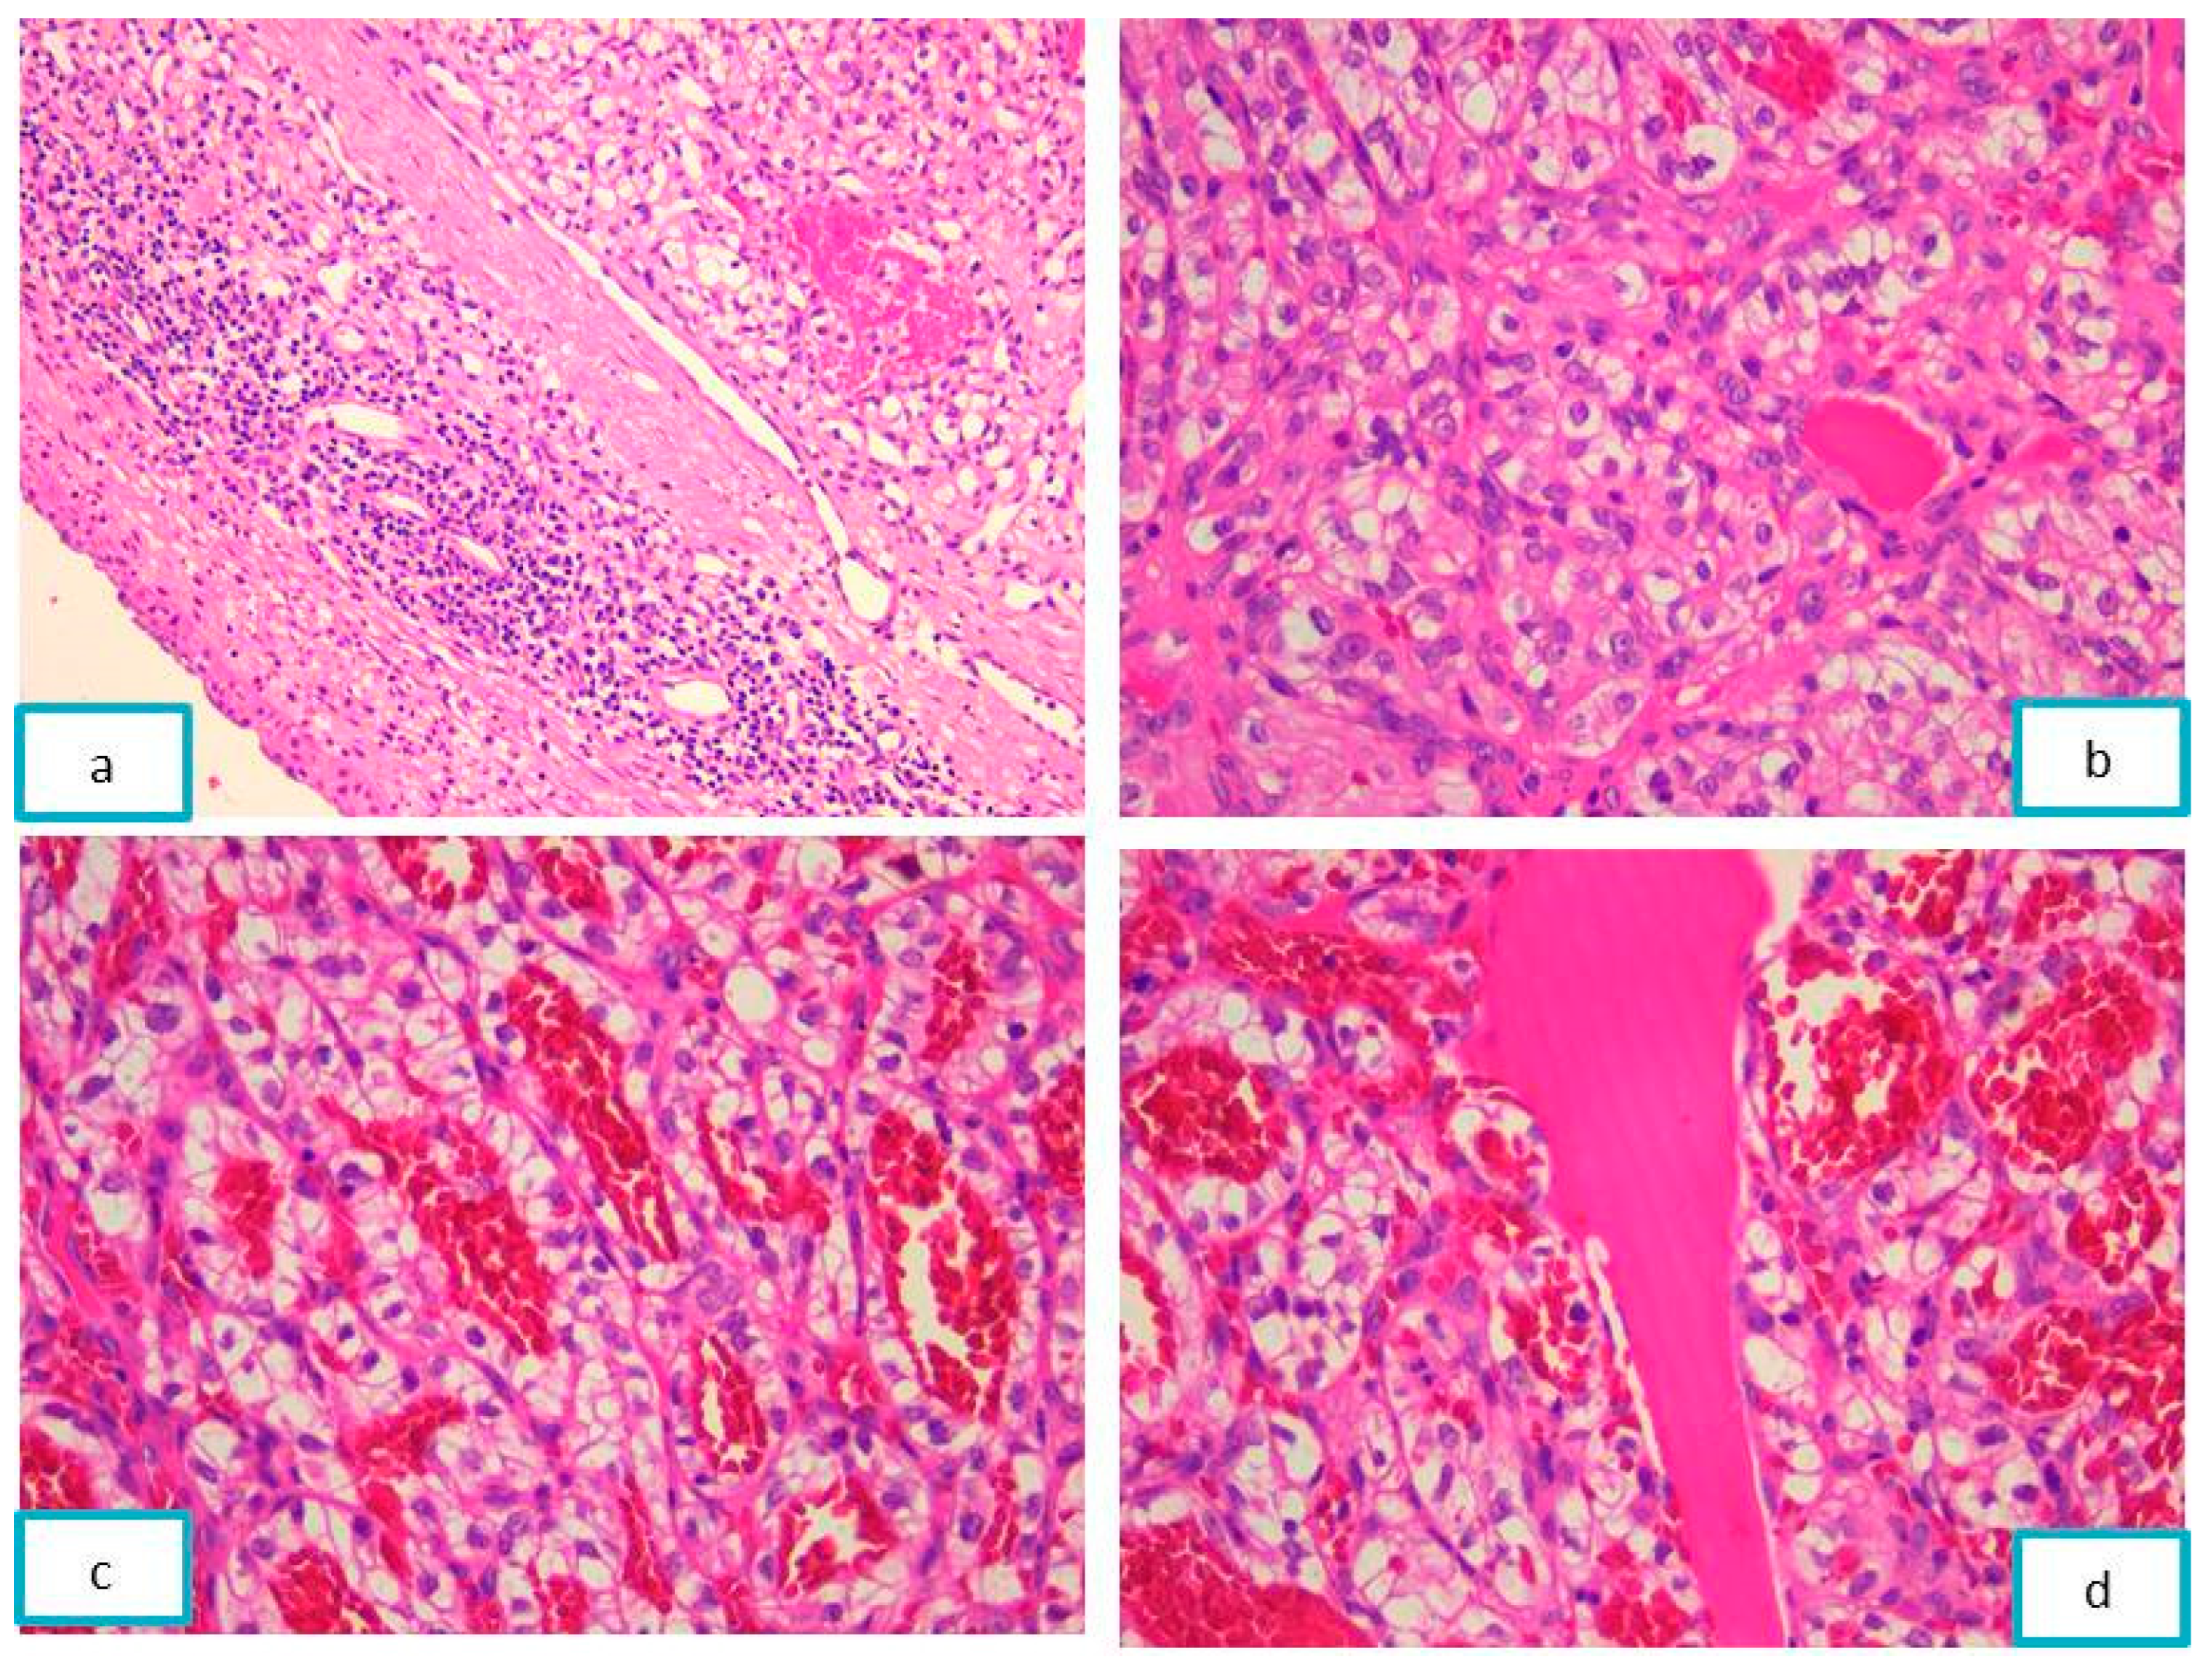

2.3.2. Pathological Findings

3.2. Jaw Bone Metastasis of Hepatocellular Carcinoma